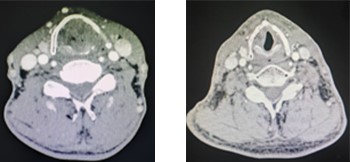

上图为患者喉癌放疗计划